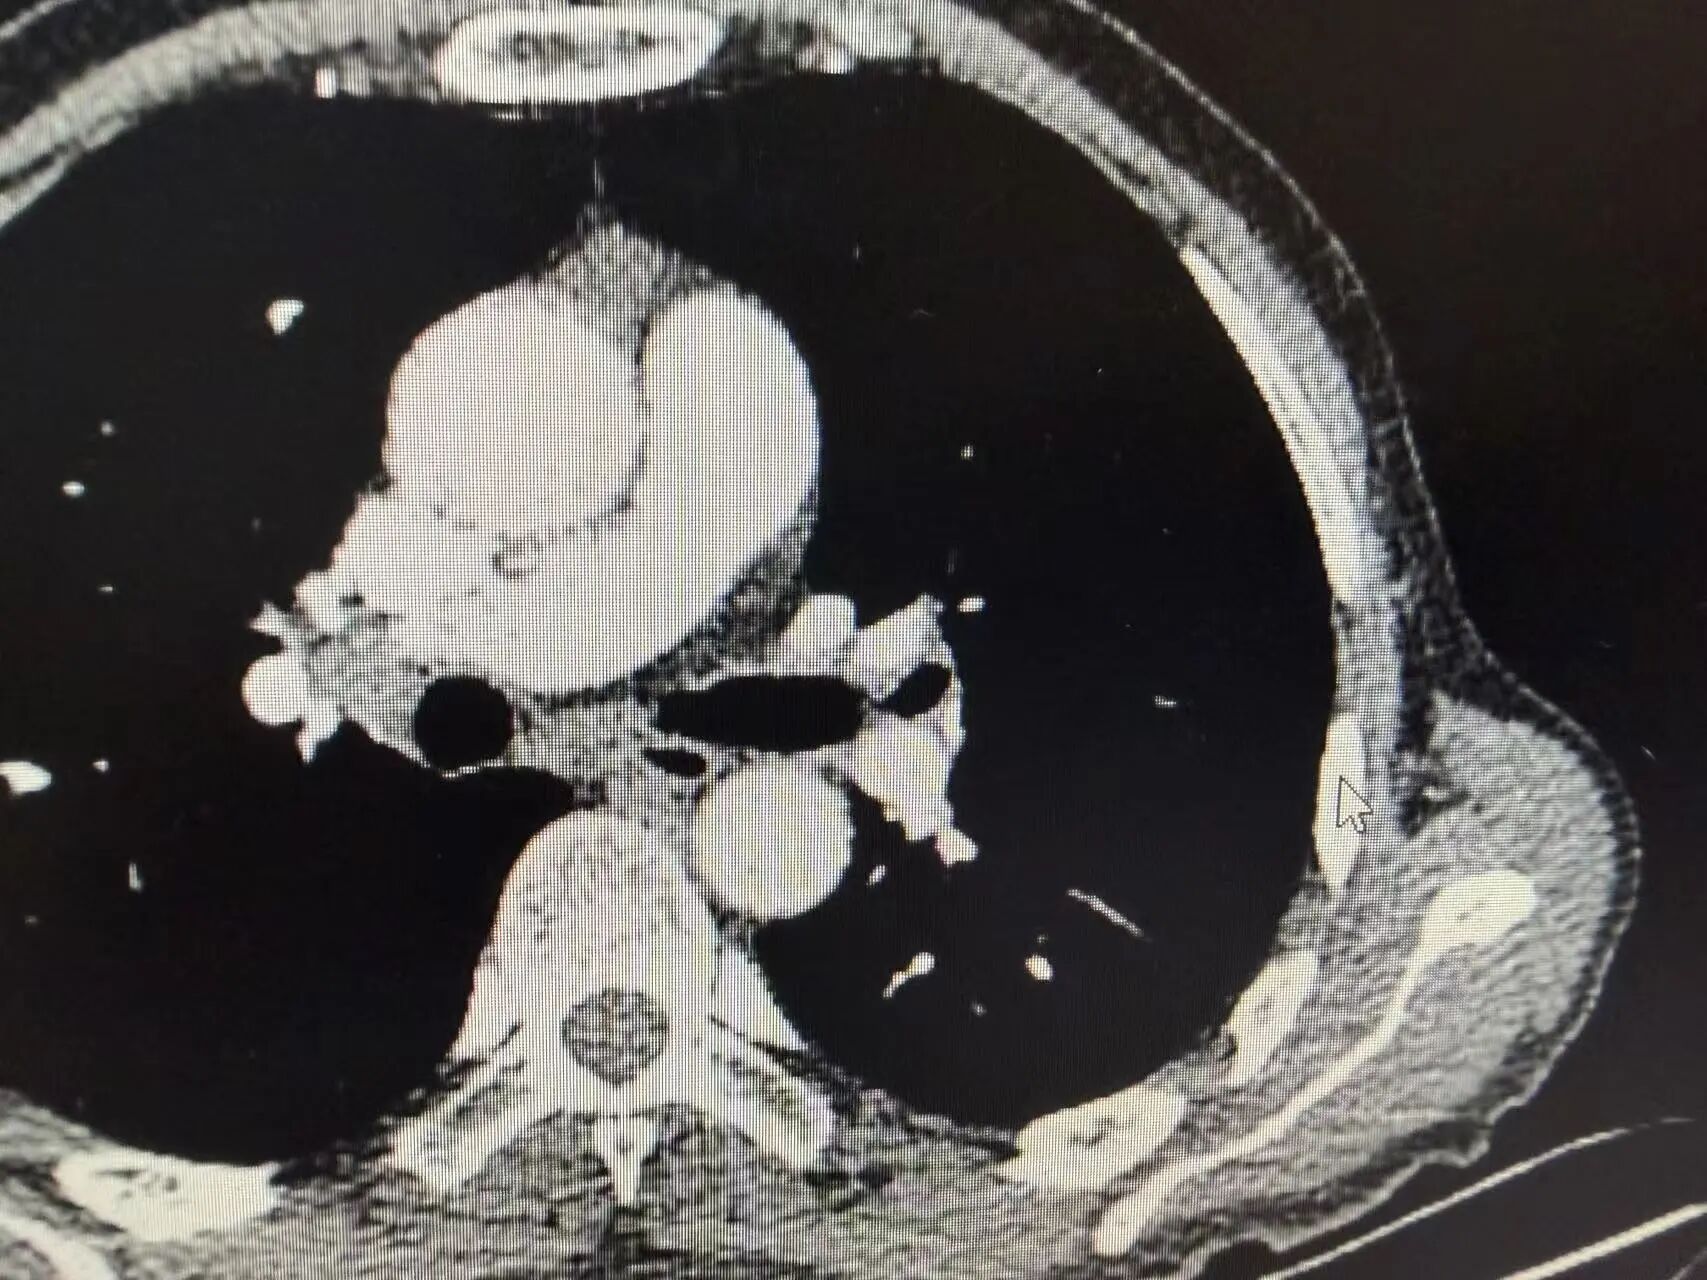

几个周期的治疗结束后,复查CT的结果传来了好消息:肿瘤明显缩小,原本粘连的血管也逐渐松动!这意味着,王叔终于获得了宝贵的手术机会,曾经的“不可切”,如今变成了“可切”。

新辅助治疗前CT:可见左上肺中央型占位,肿瘤侵犯血管

新辅助治疗后CT:肿瘤明显缩小